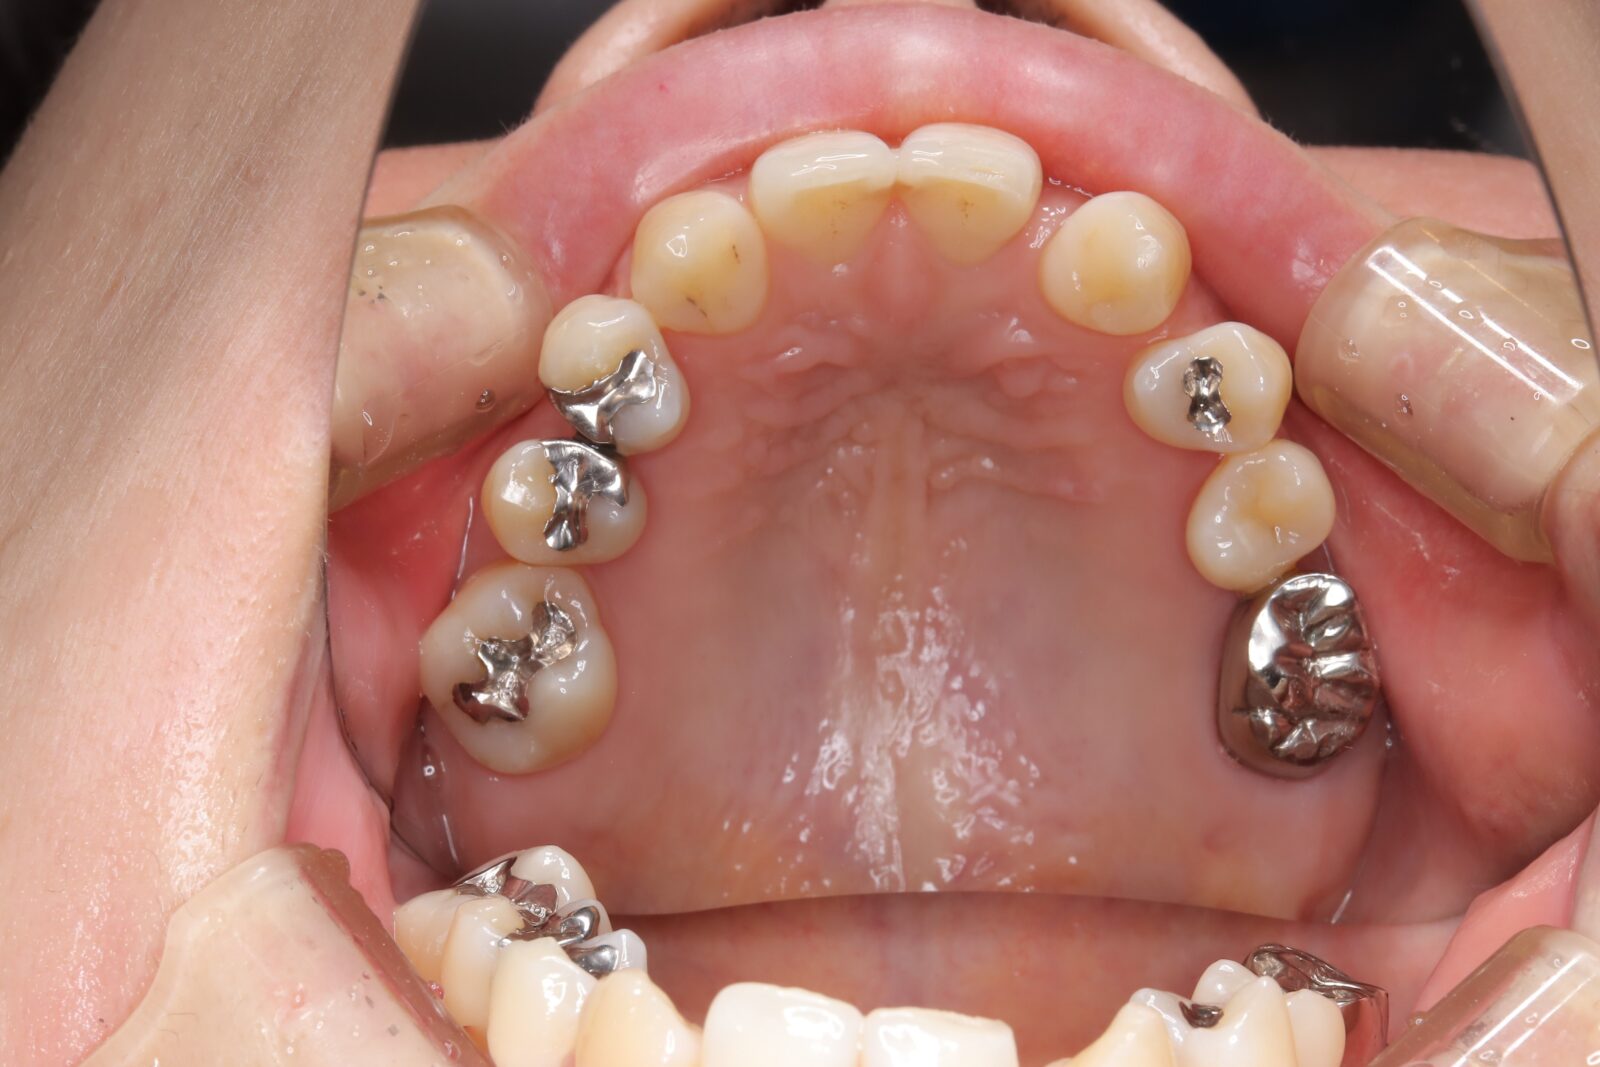

デンチャー+補綴+マウスピース矯正の症例

左上4〜7番に虫歯。右の親知らずの歯周ポケットは10mmあったため抜歯した。

左上6番の遠心は虫歯の範囲が大きすぎたため抜歯。義歯の安定を考慮すると、左上臼歯部をブリッジにするよりも、両側に義歯の人工歯を配置する方が良いと判断した。

本人の希望で薄く、口蓋を覆わない設計とした。

下顎前歯は抜歯後の治癒待ち、左上の虫歯治療中にインビザラインで歯列を整えた。

義歯作成期間中も歯の移動を行い、最終的には、計画通りに上顎の新義歯装着と同時に下顎のリテーナーを装着できた。

スマイルデンチャー

ジルコニアクラウン

インビザライン

治療期間約5ヶ月